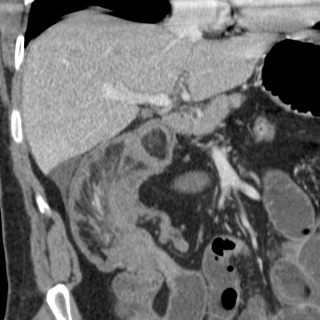

Image TDM en coupe

sagitale : Occlusion de l'intestin aigue avec

signe de bec de oiseaux ( fleche rouge ) et

dilatation intestinale en amont et signe de feces (

retention de feces au niveau de l'intestin sus -lesionelle |

Image TDM en coupe axiale :

Signe de feces' c'est la retention de fesce dans la

portion sus -lesionelle de l'intestin ( fleche

blanche ) . |